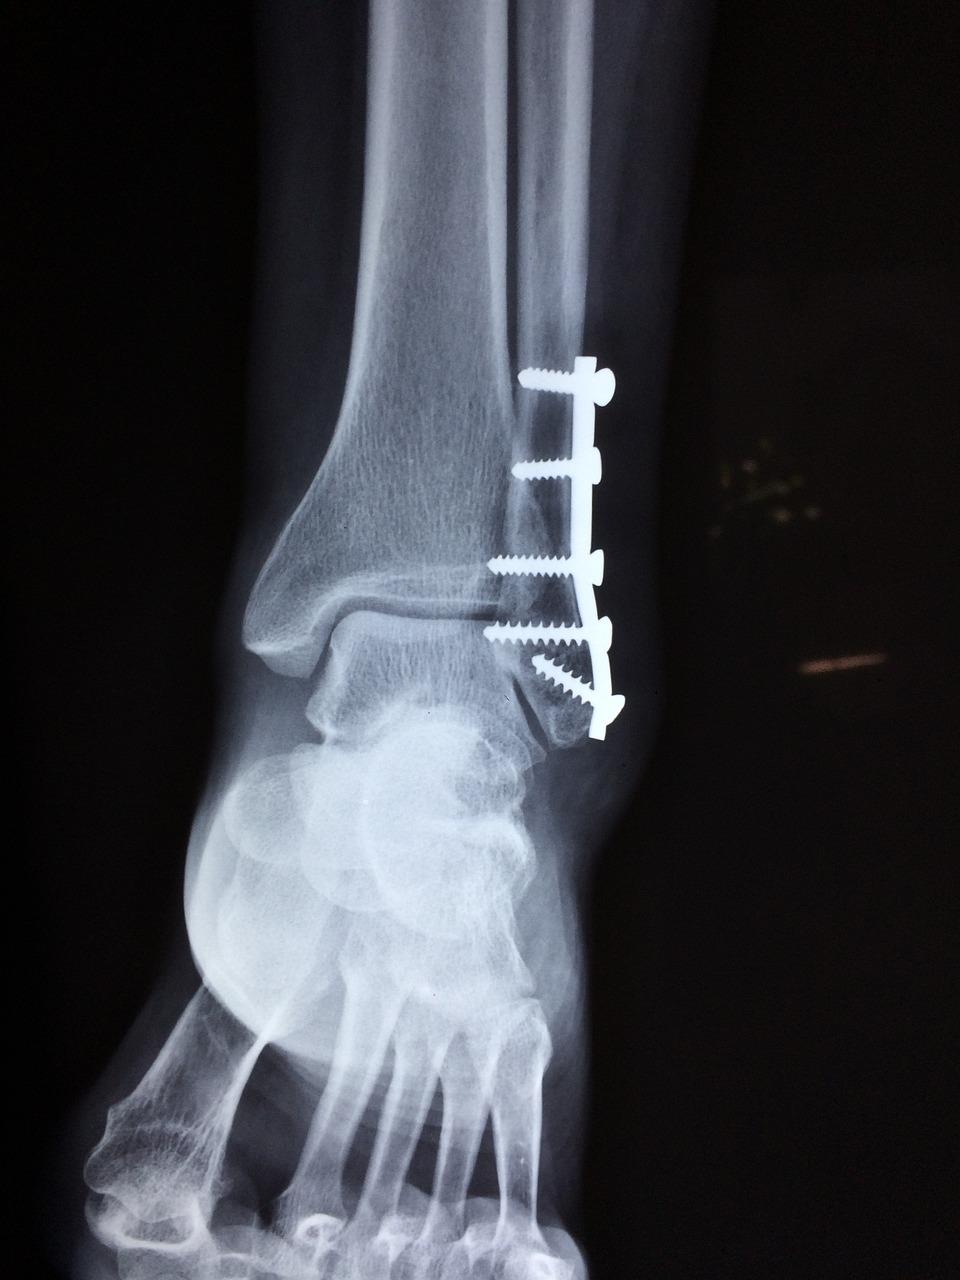

Orthopedische chirurgie voor fracturen en botbreuken

Orthopedische chirurgen in Purmerend bieden gespecialiseerde zorg voor fracturen en botbreuken. Met geavanceerde technieken en ervaring streven zij naar nauwkeurige herstelprocedures voor optimale genezing.

Van complexe breuken tot acute verwondingen, deze specialisten hebben de expertise om de juiste benadering te kiezen voor elke situatie. Vertrouw op hun vaardigheden voor een doeltreffende behandeling en revalidatie.

De focus ligt op het herstellen van functionaliteit en mobiliteit na een trauma. Ontdek de hoogwaardige orthopedische chirurgie die beschikbaar is in Purmerend voor een snel en effectief herstel.